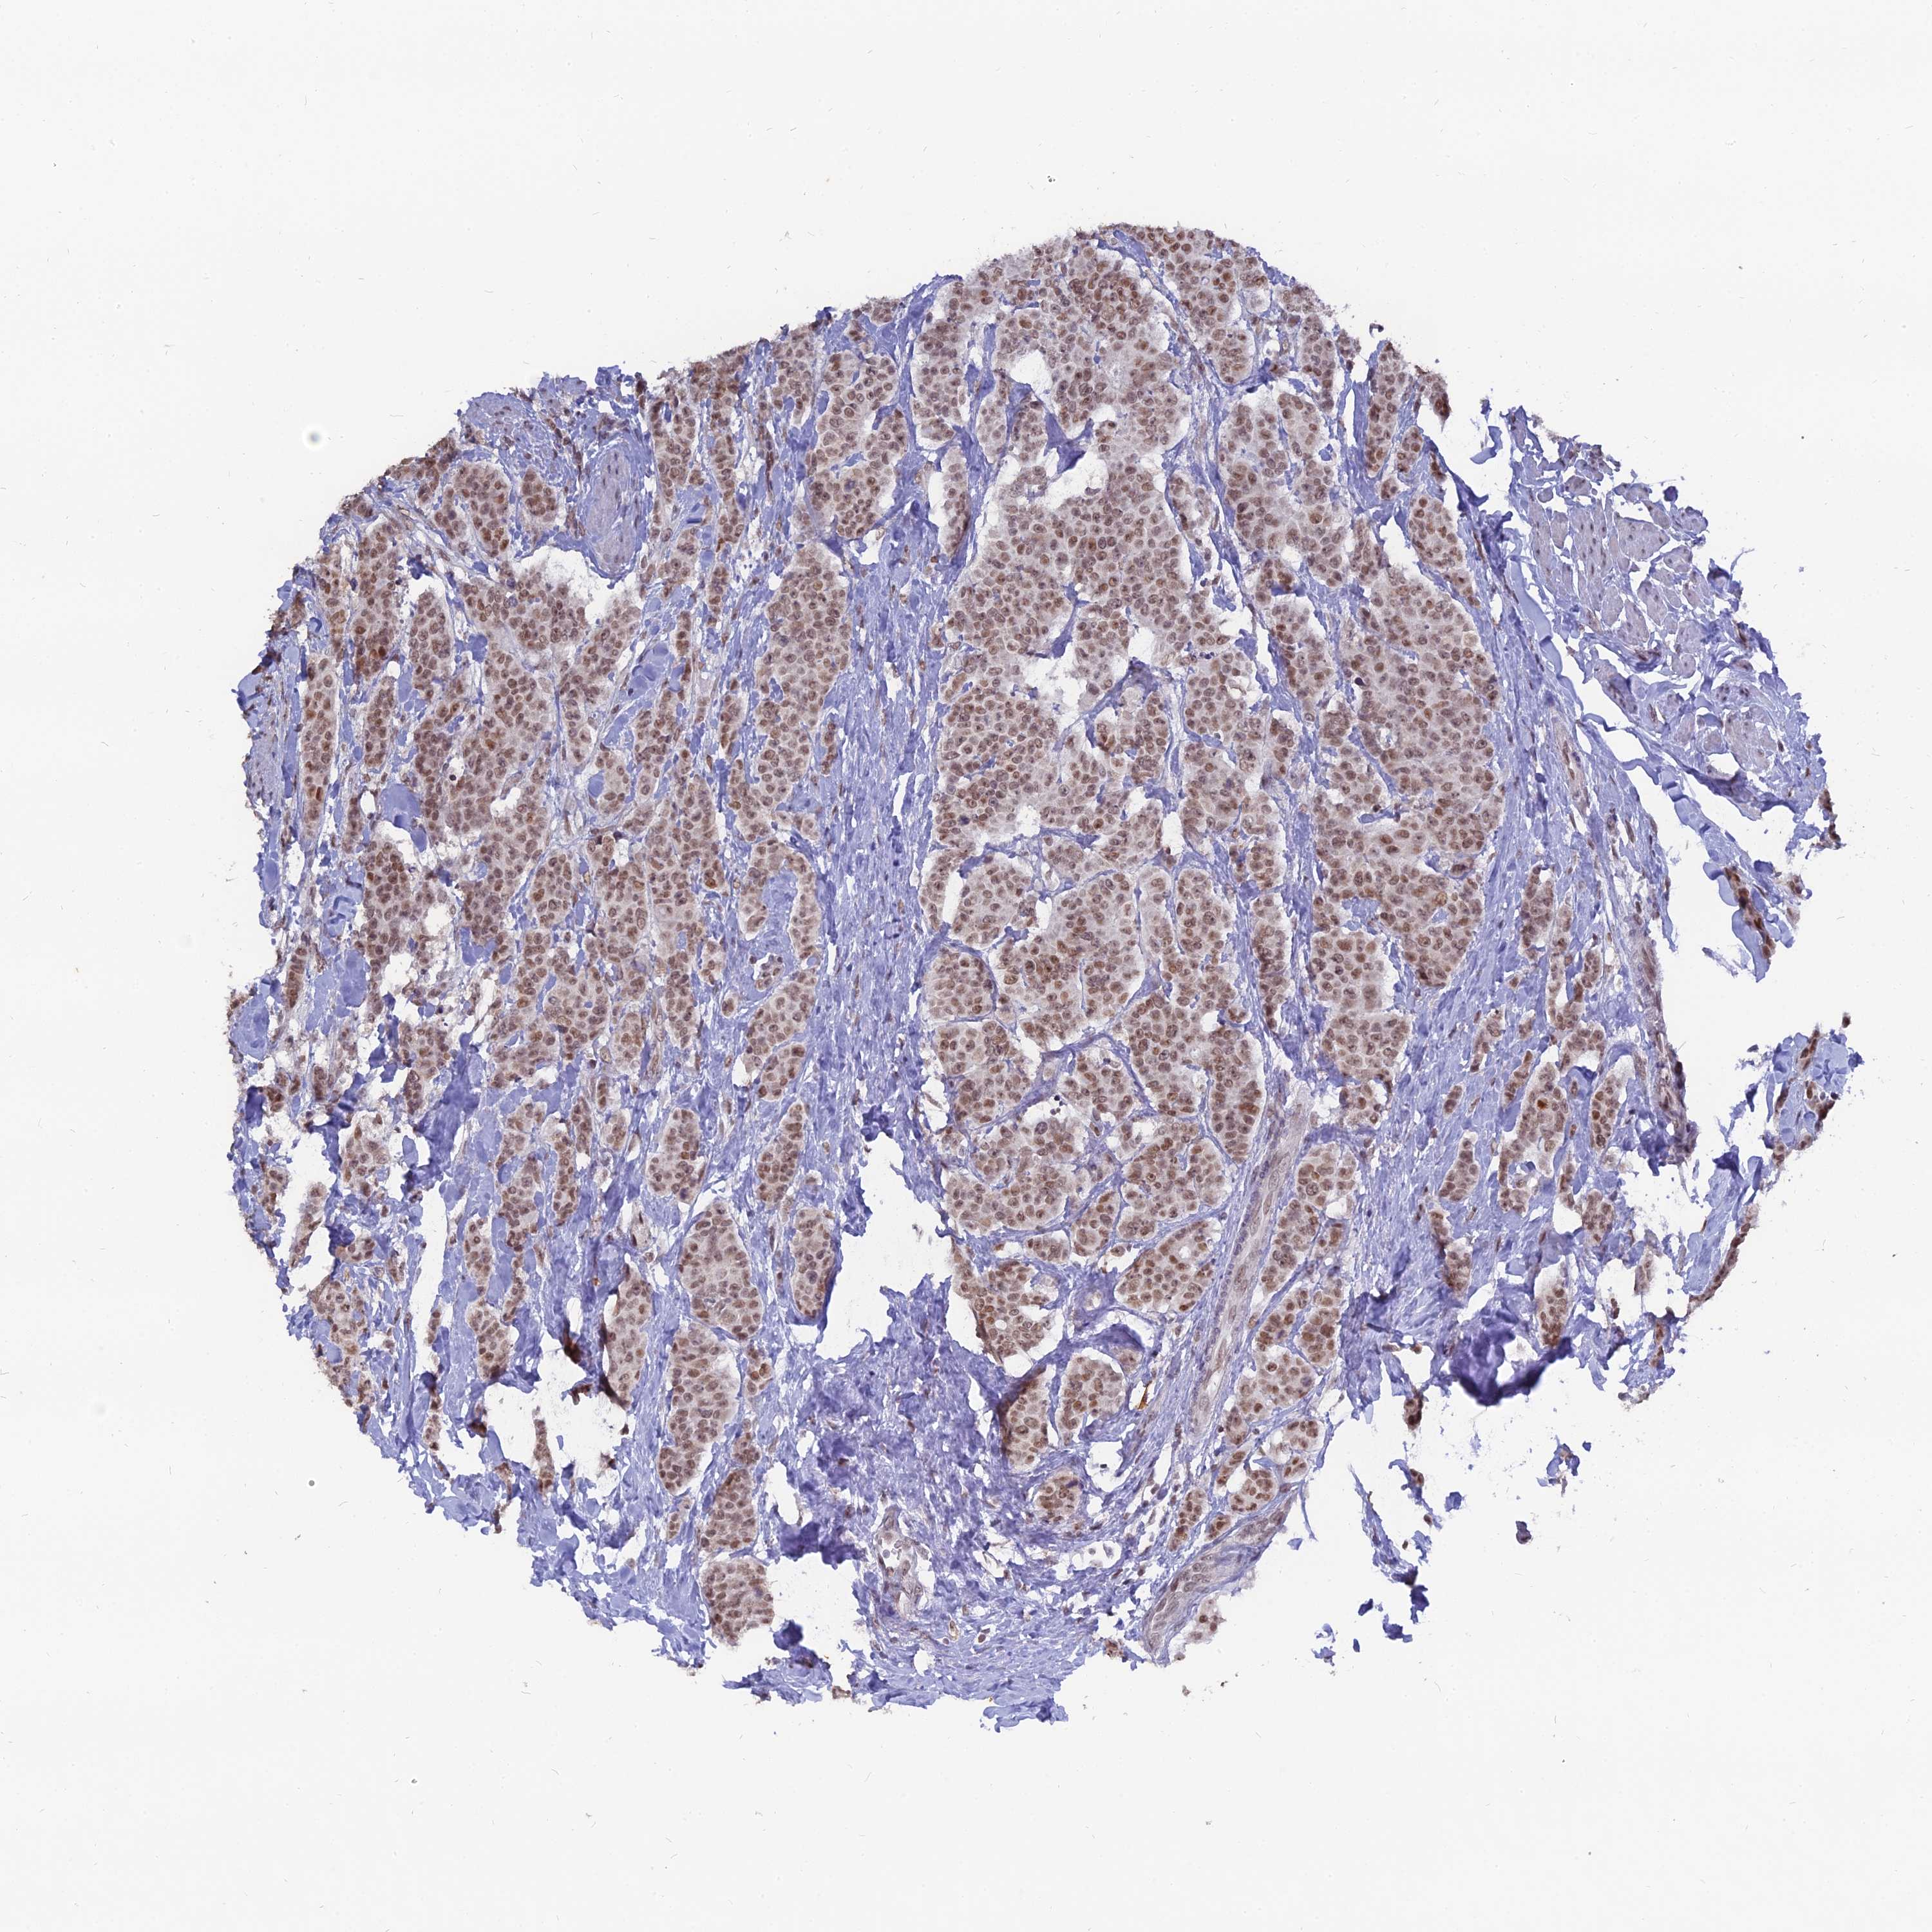

CANCER BREAST CANCER Show tissue menu

BRCA TCGA BRCA VALIDATION PROTEIN EXPRESSION